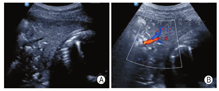

肺实变:肺组织完全失气化后表现为实性组织回声,呈大小不等的斑片状或者"肝样变",可伴有"支气管充气征"或者"支气管充液征"(图9)。

胸腔积液:超声表现为胸膜腔内低/无回声区,可见条索样分隔,脓胸时应注意与实变的肺组织鉴别(图10)。

病例1.男,77岁,因"反复发热2周"入院。体温波动于37~38.5 ℃,以下午及夜间明显。入院后行胸部CT检查提示:双肺炎症,病毒性肺炎不能除外。既往有高血压病史30余年;10年前行胆囊切除术、下肢静脉曲张手术;3年前行前列腺癌手术。近2周无武汉疫区居留史,未接触武汉返乡人员(本病例由川北医学院附属医院提供,图12)。

病例2:女,63岁,因"咳嗽、发热、畏寒4天"入院,体温最高39℃。CT:双肺多叶段散在斑片状磨玻璃影,以右肺下叶为主,双侧胸膜增厚。既往有"高血脂"、"甲状腺功能减退",17年前行"子宫全切术"。出生并久居武汉,2020年1月18日到成都旅游,之前未接触类似发热患者(本病例由成都市公共卫生医疗中心提供,图13)。

病例3:男,50岁,因"尿少2年,心累、气促1月、发热、咳嗽2天"入院,体温最高38.5 ℃。2020年1月15日院外胸部CT示:双肺散在模糊小结节,双肺下叶感染,双侧胸腔少量积液;2020年1月2日院外复查CT示:双肺感染灶明显进展,呈散在结节斑片影,部分结节内可见空洞,空洞内可见内容物;2020年2月4日复查CT:双肺散在斑片、磨玻璃、点结、纤维条影,密度不均,边界模糊,双侧胸腔少量积液,心包腔少量积液。既往有"肾功能不全尿毒症期""高血压病3级""2型糖尿病"等。1月前因慢性肾功能衰竭在武汉某三甲医院ICU住院治疗17天,于2020年1月13日到成都某医院因重症肺炎、病毒性肺炎、慢性肾病住院治疗8天后,以"新型冠状病毒肺炎疑似患者"到定点医院隔离治疗,后核酸检测阳性确诊(本病例由成都市公共卫生医疗中心提供,图14)。